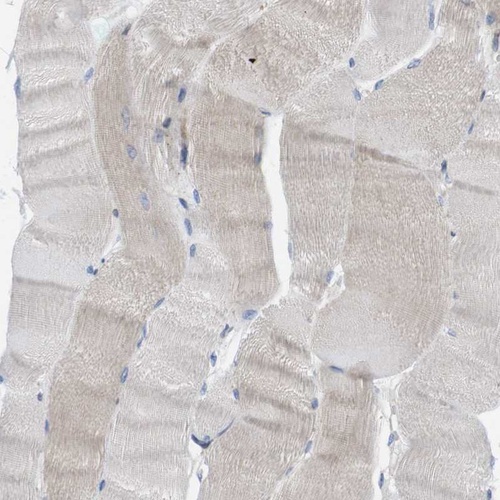

Immunohistochemistry analysis in human cerebral cortex and skeletal muscle tissues using HPA014837 antibody. Corresponding HACD3 RNA-seq data are presented for the same tissues.